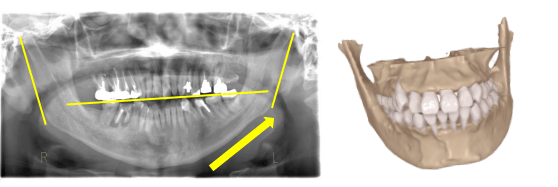

足の長さのずれは整体で治りますが、次の日にはまた戻ってしまいます。

しかし、整体された状況下で顎の位置の記録をとることで、姿勢は崩れにくくなります。